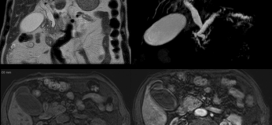

ADENOCARCINOMA ABDOMINAL

El adenocarcinoma abdominal. Recordemos que la Trofología avanzada (binipatia), tiene el extraordinario poder de eliminación de las células cancerígenas (tumores), al igual que su maravillosa estrategia para detener el cáncer, al provocar la muerte de las células del cáncer por hambre. Esta es la maravillosa estrategia de la Trofología avanzada, hacer morir de hambre al cáncer mientras alimenta a las …